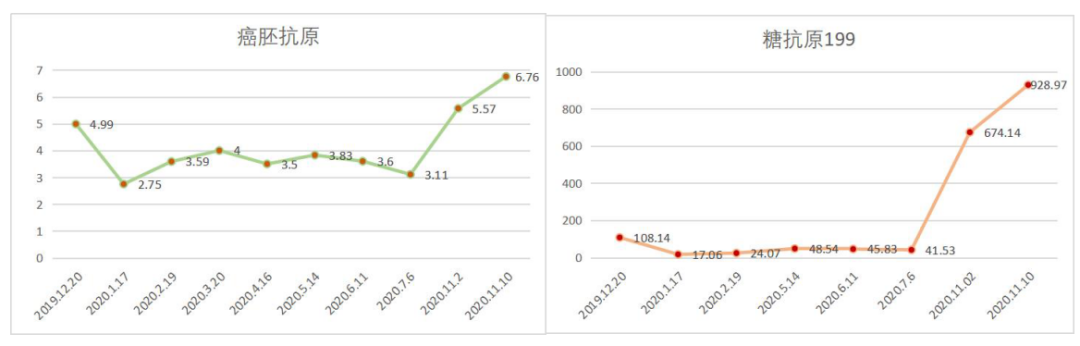

定期复查肺部和全腹部CT未见明显复发病灶,肿瘤标志物CEA和CA199升高,下一步治疗?

2019-12-20至2020-7-6行SPA+赫赛汀 q3w 8周期联合化疗:白蛋白紫杉醇250mg、替吉奥3# BID D1-14、赫赛汀 300mg D1 。

2019-12-20至2020-7-6

影像学评估:胃癌术后改变。持续CR。

肿瘤标记物评估:肿瘤标记物明显下降。

末次化疗时间为2020-7-6,定期复查于2020-11发现标记物明显升高,影像学提示疾病进展。